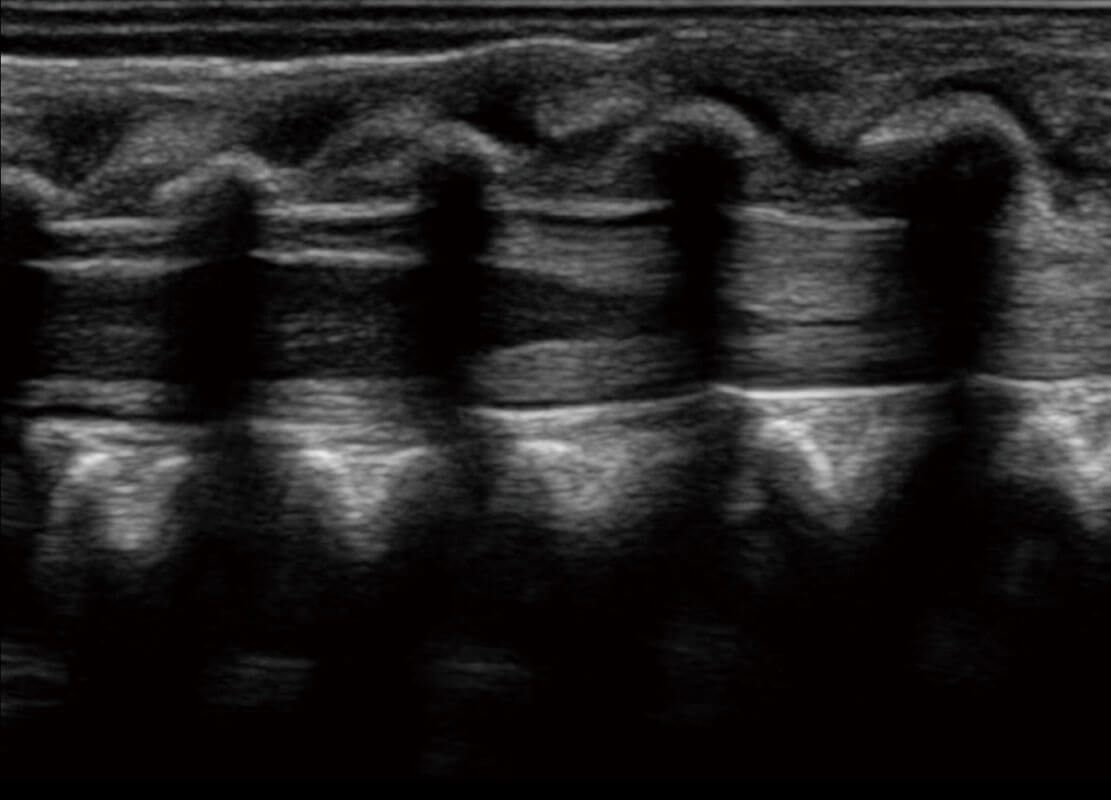

P60优异的图像质量搭载专科探头,在妇科基础疾病的诊断、卵泡生长的监测、输卵管通畅情况的判别等方面为您提供生殖应用方案。

腔内妇科-宫腔分离

腔内妇科-卵巢

腔内三维-宫内节育器

腔内三维-光影成像